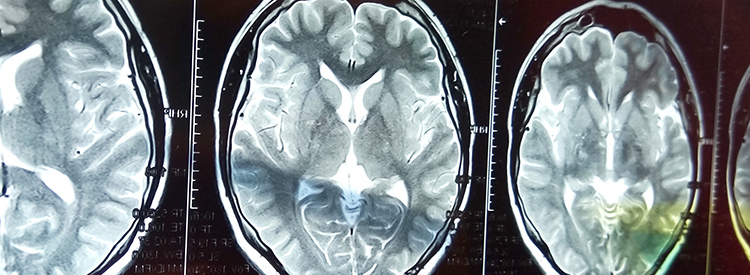

當(dāng)大腦部分血流被切斷時,就會發(fā)生中風(fēng)。當(dāng)這種情況發(fā)生時,失去血液供應(yīng)的腦組織就會受傷或死亡。根據(jù)大腦受損區(qū)域控制的功能,這會導(dǎo)致身體功能喪失。例如,如果控制左臂運動的區(qū)域受損,該臂就會變得虛弱或癱瘓。如果左臂控制感覺的區(qū)域也受到影響,手臂會麻木,或者也可能有燒灼感或疼痛感。由于大腦控制著我們所有的運動和感覺,包括視覺和言語,因此幾乎任何事物都可能受到中風(fēng)的影響。

中風(fēng)治療進(jìn)展緩慢。如果在最初幾分鐘內(nèi)進(jìn)行治療,可以在急診室或醫(yī)院使用特殊藥物(阿替普酶或組織纖溶酶原激活劑)來逆轉(zhuǎn)或限制缺血性中風(fēng)造成的損害。這種藥物可以分解阻塞血管的凝塊。如果在最初的幾分鐘到幾小時內(nèi)使用,可以避免或限制對大腦的任何損害。在使用阿替普酶之前,必須進(jìn)行 CT 成像來確定中風(fēng)類型,以確認(rèn)中風(fēng)不是出血性的。由于阿替普酶會分解血栓,因此如果用于出血性中風(fēng),可能會導(dǎo)致嚴(yán)重惡化或死亡。有時會治療出血性中風(fēng)以避免進(jìn)一步出血。